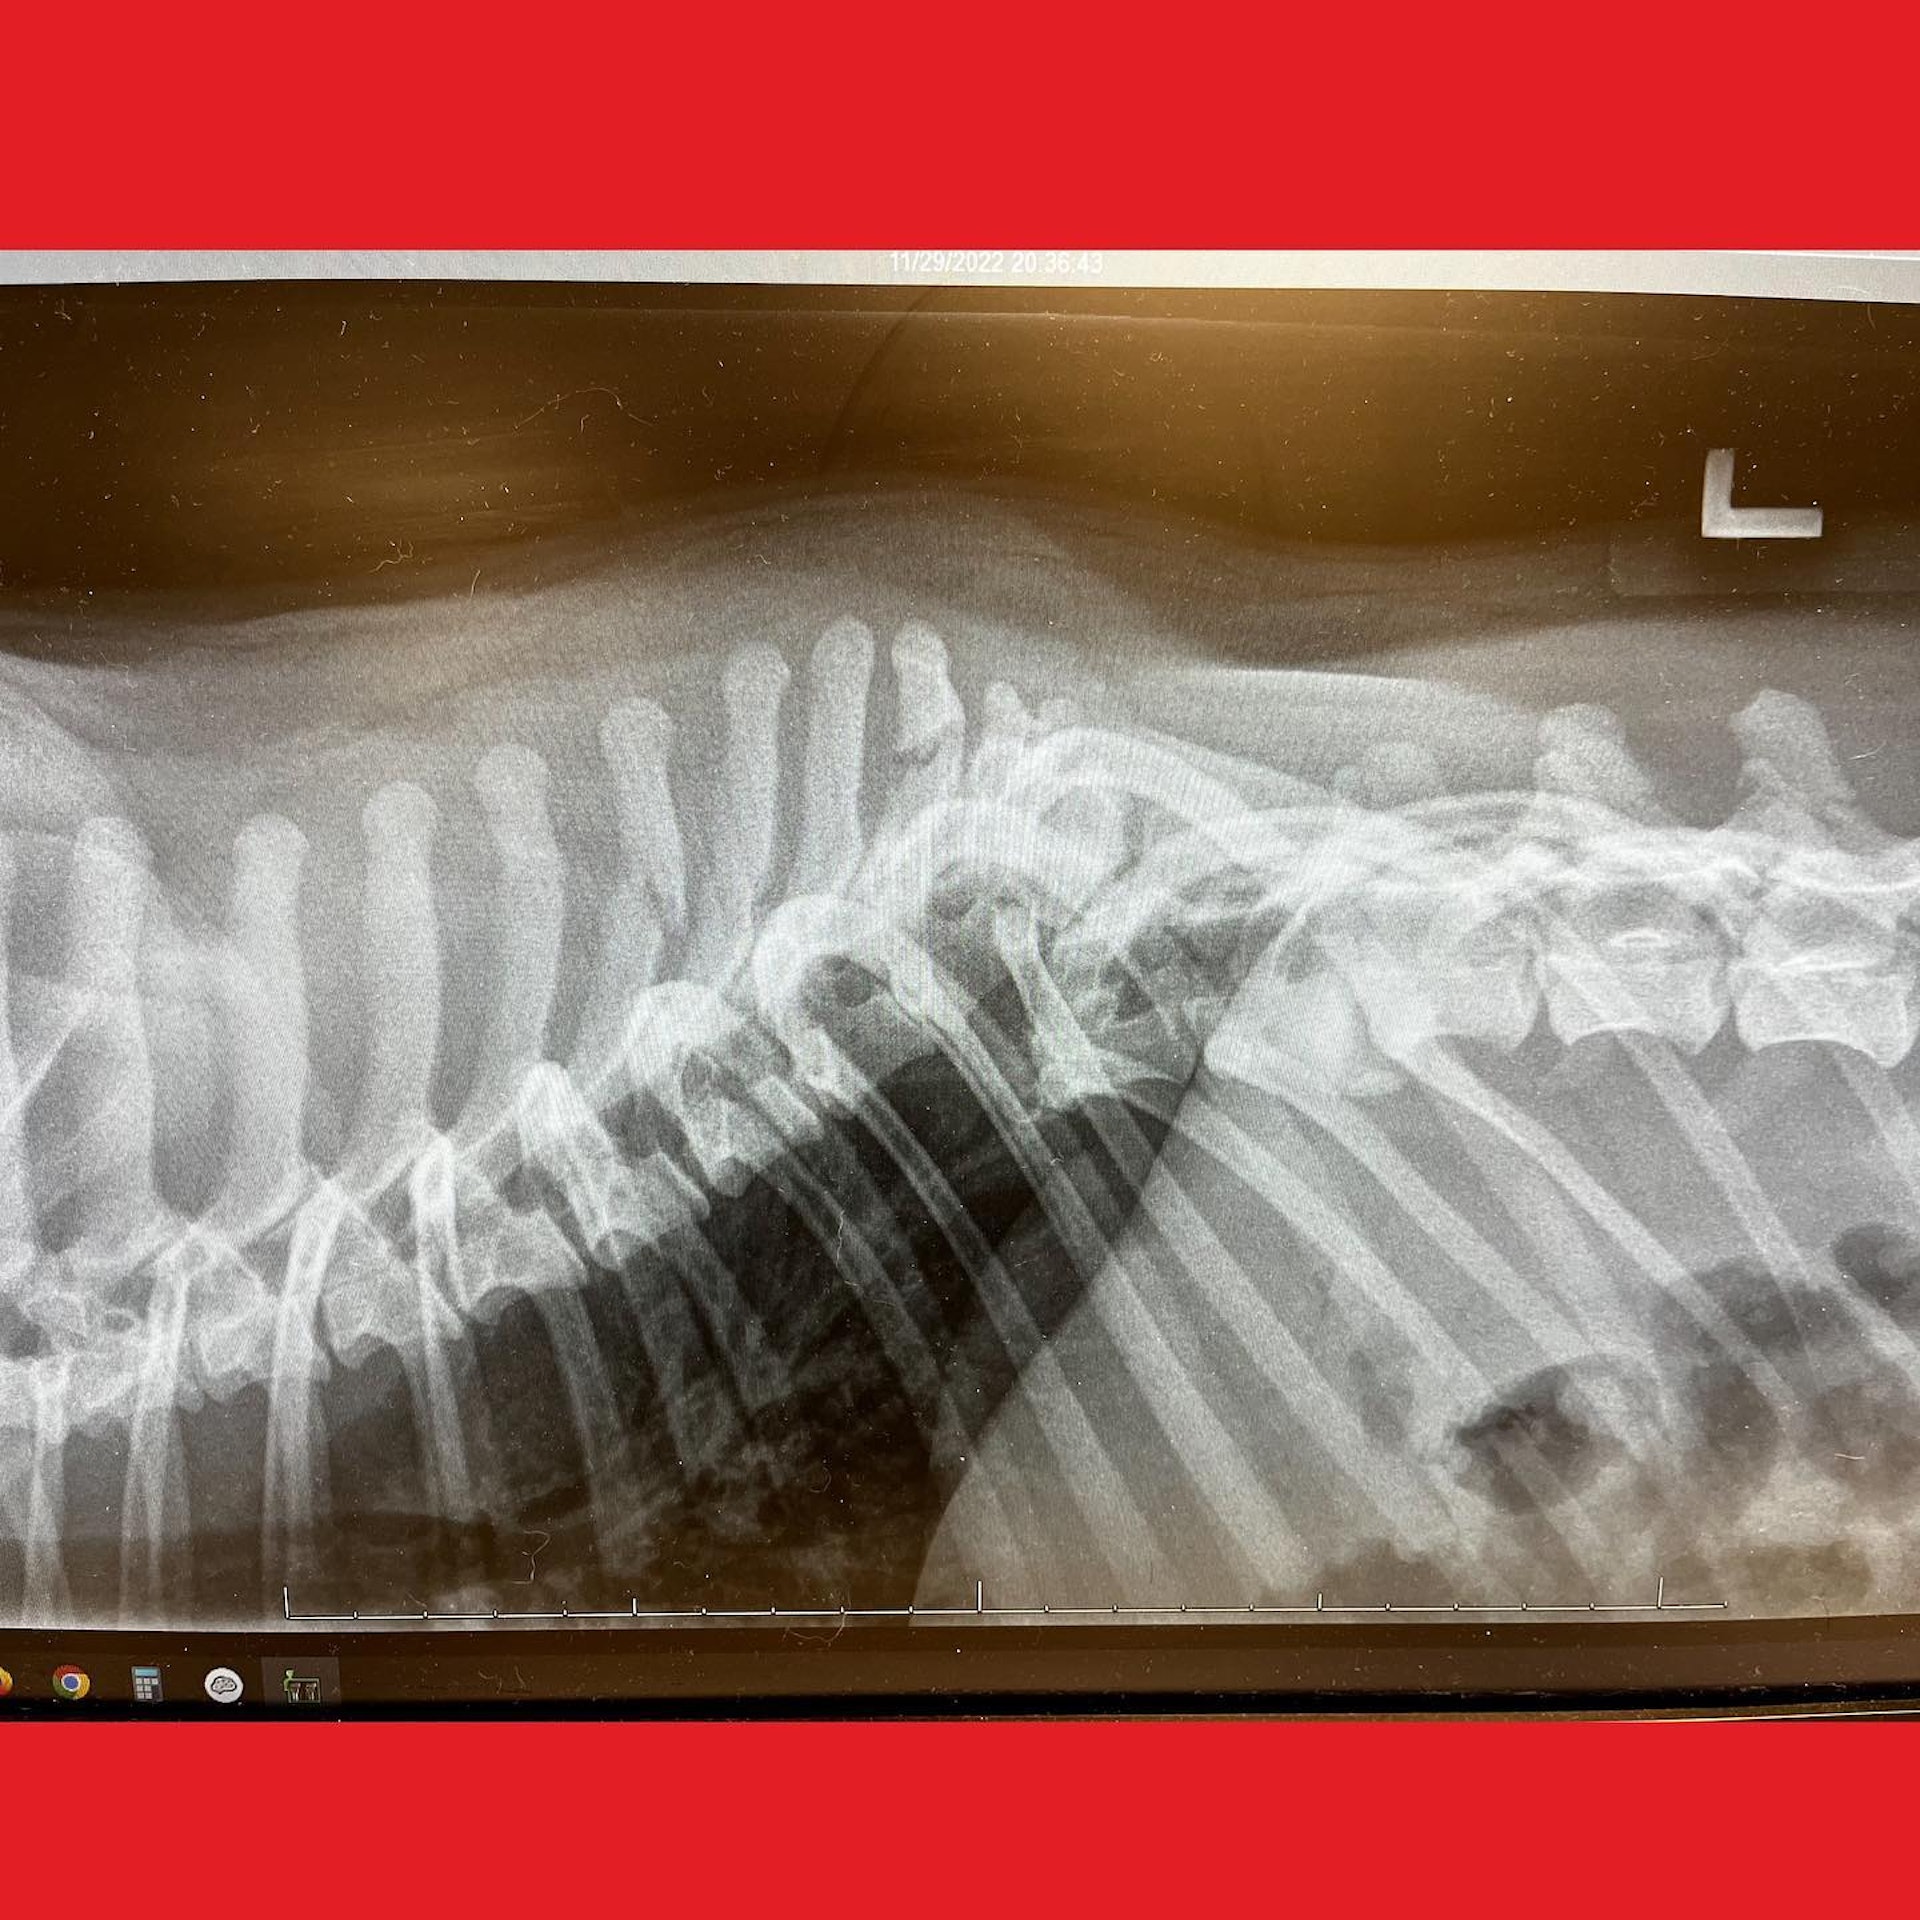

Then the X-rays revealed devastating news.

His spinal cord had been completely severed.

Veterinarians described it as one of the most severe spinal fractures they had ever seen. Even worse, he was at high risk of developing a deadly neurological condition known as myelomalacia.

Surgeons carefully installed two metal plates along his shattered spine, stabilizing the damaged bones and giving his body a chance to heal.